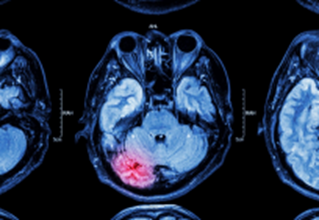

Traumatic brain injury (TBI) affects a multitude of people around the world, and many studies have placed the number in the millions (Galgano et al. 2017). The groups most affected by TBI include the younger populations ranging from very young, between 0 to 4 years of age, and between 15 to 24 years old (Galgano et al. 2017). Although, according to the National Library of Medicine, there is a discrepancy between the actual number of cases and the number of reported cases, as many cases go unreported (Galgano et al. 2017). Many levels of traumatic brain injury can have minimal effects to serious consequences on the individual (Galgano et al. 2017).